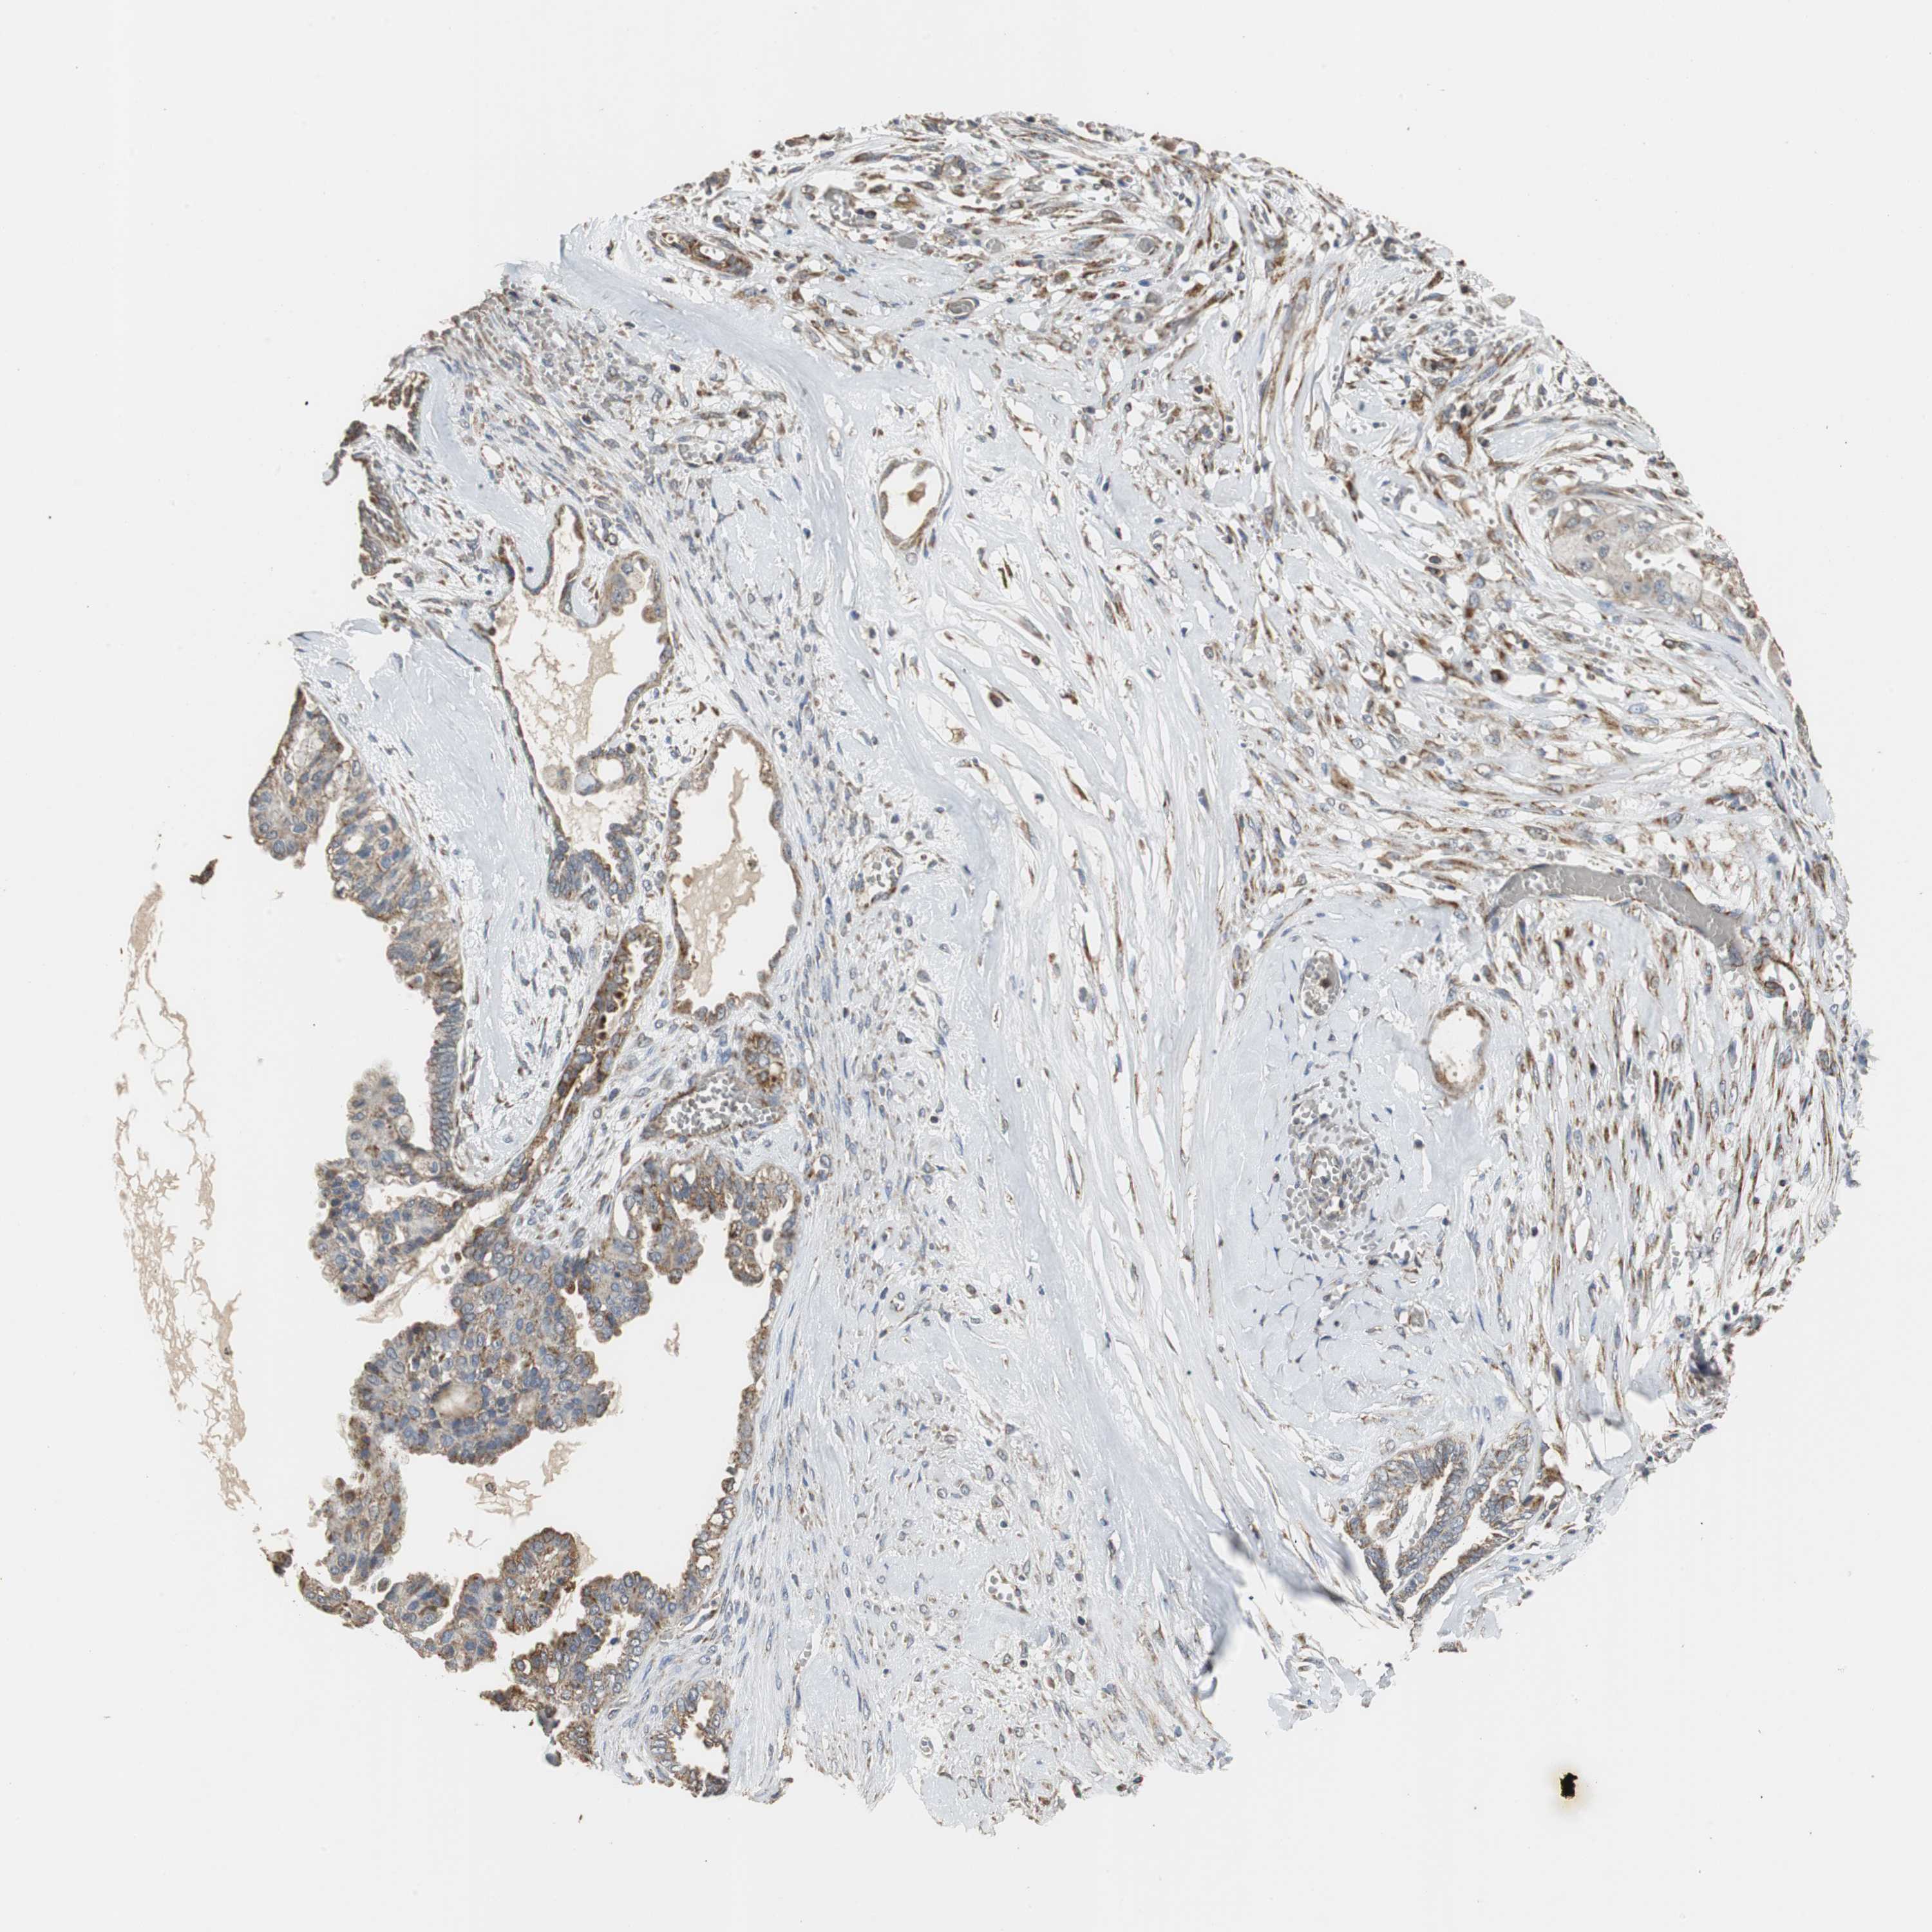

OVARIAN CANCER - Protein expressioni

A mouse-over function shows sample information and annotation data. Click on an image to view it in a full screen mode. Samples can be filtered based on level of antibody staining by selecting one or several of the following categories: high, medium, low and not detected. The assay and annotation is described here.

Note that samples used for immunohistochemistry by the Human Protein Atlas do not correspond to samples in the TCGA dataset.

Antibody stainingi

Antibody staining in the annotated cell types in the current human tissue is reported as not detected, low, medium, or high, based on conventional immunohistochemistry profiling in selected tissues. This score is based on the combination of the staining intensity and fraction of stained cells.

Each image is clickable and will lead to virtual microscopy that enables deeper exploration of all samples and also displays staining intensity scores, fraction scores and subcellular localization as well as patient and tissue information for each sample.

Antibody HPA004829

Antibody CAB004975

Staining

High

Medium

Low

Not detected

Intensity

Strong

Moderate

Weak

Negative

Quantity

>75%

75%-25%

<25%

None

Location

Nuclear

Cytoplasmic/membranous

Cytoplasmic/membranous,nuclear

Cystadenocarcinoma, serous, NOS

Carcinoma, endometroid

Carcinoma, NOS

Cystadenocarcinoma, mucinous, NOS